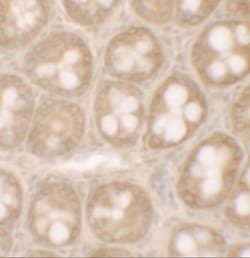

STAT3 Polyclonal specifically detects STAT3 in Human, Mouse, Rat samples. It is validated for Western Blot, ELISA, Immunohistochemistry, Immunocytochemistry/Immunofluorescence, Immunohistochemistry-Paraffin.

| Western Blot, ELISA, Immunohistochemistry, Immunocytochemistry, Immunofluorescence, Immunohistochemistry (Paraffin) | |

| Western Blot 1 - 2 μg/mL, ELISA, Immunohistochemistry, Immunocytochemistry/Immunofluorescence, Immunohistochemistry-Paraffin | |